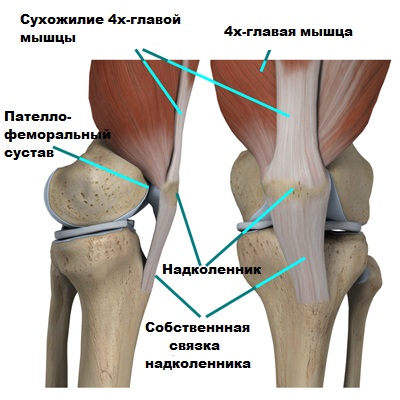

Сустав, образующий колено, сформирован верхним участком большеберцовой и нижним фрагментом бедренной костей, надколенником (одним из наиболее крупных сесамовидных костных образований), а также окружающими их мышечными тканями и сухожилиями.

Разгибательную функцию колена выполняют сухожилие четырехглавой мышцы, непосредственно сама четырехглавая мышца, а также прикрепленная к большеберцовой кости собственная связка коленной чашечки.